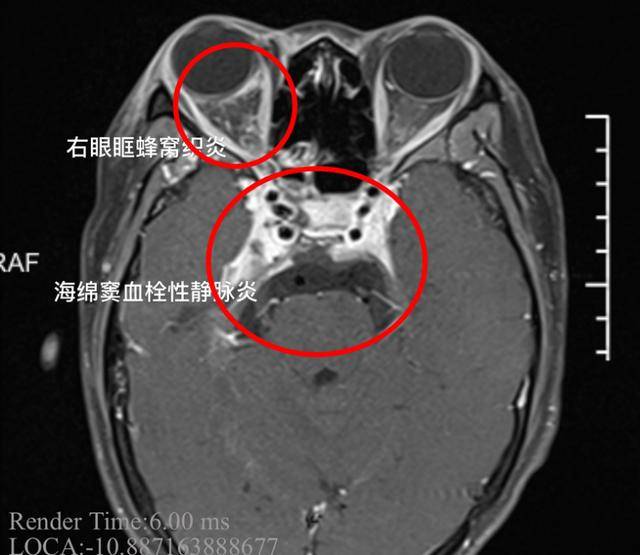

据媒体报道,宁波宁海一名19岁女孩,鼻子上长了个疙瘩,顺手挤了出来。没想到右眼周围的皮肤开始红肿疼痛,体温一下子飙升到39.7℃,右眼肿了,眼睛睁不开。

然后女孩立刻去了医院。经诊断,该女孩患有“海绵窦血栓性静脉炎”,并被送往医院。

医生解释:这是严重的颅内感染。如果不及时治疗,病人可能会死亡。同时,患者的脑膜刺激征为阳性,表明炎症已在海绵窦内扩散,出现脑膜炎,会一直担心生命。